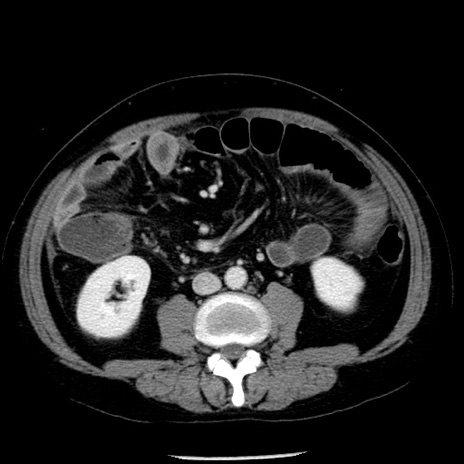

症例29(横断像)

【症例】40歳代男性

【現病歴】2日前から胃痛あり。徐々に周期的な激痛に変化した。本日になっても激痛があるため受診。

【身体所見】意識清明、BT 38-39℃台あり、腹部:膨満、やや硬、右下腹部に圧痛あり。

【データ】WBC 8500、CRP 23.26